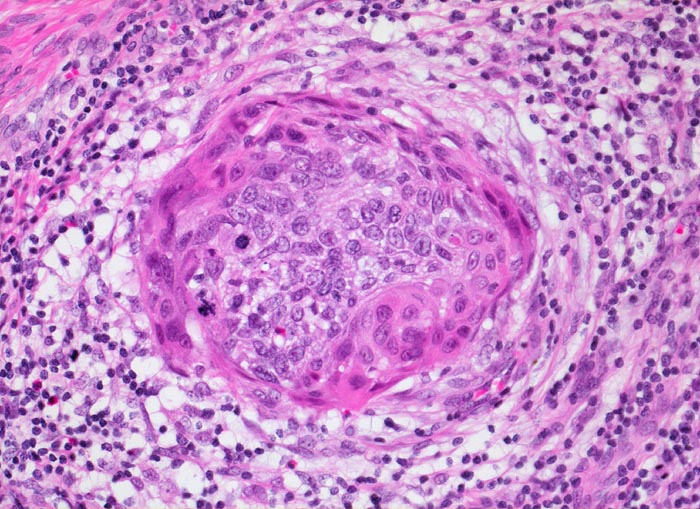

Das Carcinoma in situ wird in der Bethesda Klassifikation zusammen mit der mittelschweren und der schweren Dysplasie eingeteilt als high grade squamous intraepithelial lesion (HSIL). Im Vergleich zur schweren Dysplasie nehmen Grösse und Hyperchromasie der Kerne weiter zu. Die Zellgrösse entspricht dem Basalzelltyp. Das Chromatin ist grob verklumpt und unregelmässig verteilt. Der Kernhintergrund ist hell. Dadurch entsteht die an ein Leopardenfell erinnernde Kernstruktur. Grosse Nukleolen sind verdächtig auf eine bereits vorhandene Mikroinvasion (zweites Bildbeispiel). Zytologische und histologische Aufnahmen stammen von verschiedenen Patientinnen.